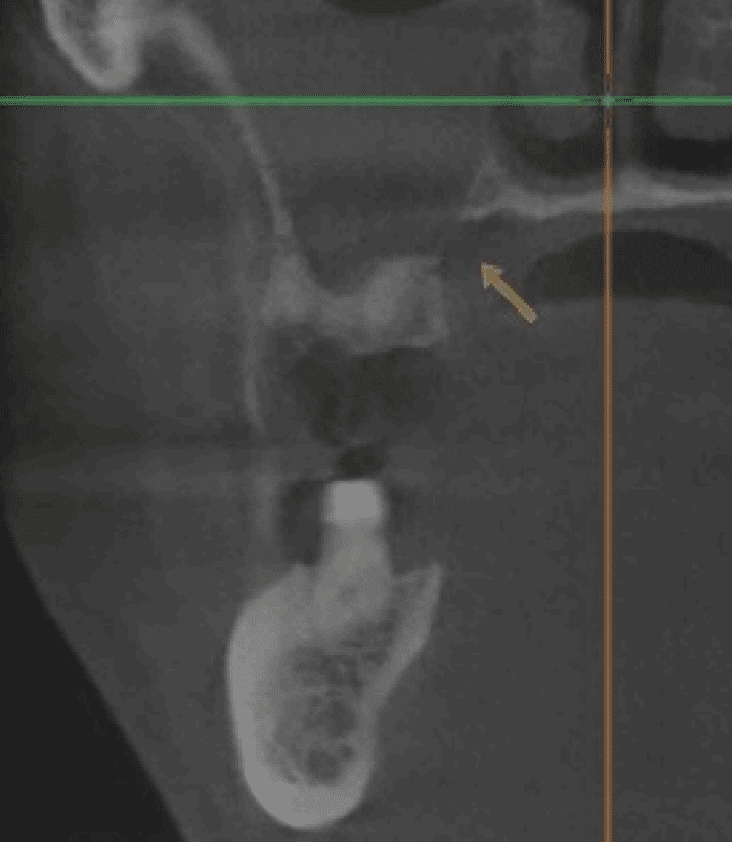

CT showed sinus opacity and cortical break in right maxillary sinus—a finding concerning for aggressive bone destruction that can indicate leukemic infiltration or pathologic bone resorption; ENT referral made.

- Osteolytic lesions with ill-defined borders and bone destruction are the most common radiographic findings[9][10]

- Cortical bone erosion or destruction, including breaks in the cortical plate, may indicate leukemic infiltration or aggressive bone resorption[9][10][11]

- Diffuse osteopenia and loss of trabecular pattern[12][13]

Cortical bone destruction in leukemia results from multiple mechanisms: direct leukemic cell infiltration, increased osteoclast activity mediated by cytokines (particularly TNFα and RANKL), and impaired osteoblast function.[14][15][16] When cortical breaks are identified in patients with suspected malignancy, they may represent aggressive disease requiring urgent evaluation.[9][11]